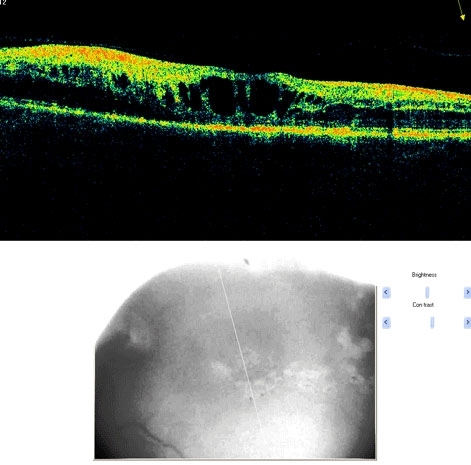

Branch Retinal Vein Occlusion

A branch retinal vein occlusion is a blockage of the portion of the circulation that drains the retina of blood. The arteries deliver blood to the retina. The red blood cells and plasma then course through the capillaries and eventually into the venous system, eventually reaching the central retinal vein. With blockage of any vein, there is back-up pressure in the capillaries, which leads to hemorrhaging and fluid leakage on the retina. Usually, the occlusion occurs at a site where an artery and vein cross. Typically, the artery crosses over the vein so that any hardening of the artery compresses the vein (which has a thinner wall). The occlusion site determines the extent or distribution of the hemorrhage, ranging from a small branch veins giving rise to occlusions involving part of the retina to a hemispheric (hemi-retinal) occlusion involving one half of the retina, to an occlusion of the central retinal vein, which involves the entire retina (when the central vein is involved, this is called a central retinal vein occlusion which is discussed below).

Branch retinal vein occlusions are by far the most common cause of retinal vascular occlusive disease. Males and females are affected equally. Most occlusions occur after age 50, although younger patients are sometimes seen with this disorder (in this age group it is often called papillophlebitis). The highest rate of occurrence is in individuals in their 60's and 70's. These disorders are similar to those for vascular occlusive disease elsewhere in the body such as stroke and coronary artery disease. Specifically, aging, high blood pressure, diabetes, and smoking are all risk factors. It is very important to find out if there is an underlying cause to any vascular occlusive disease.